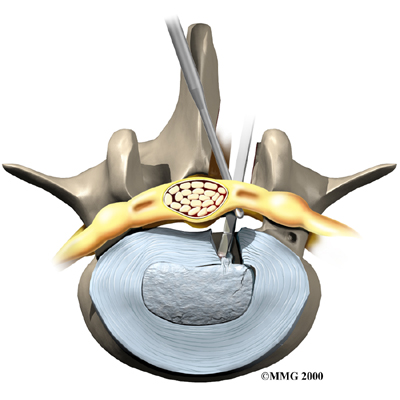

Microdiscectomy

Microdiscectomy is becoming the standard surgery for lumbar disc herniation. The procedure is used when a herniated disc is putting pressure on a nerve root. It involves carefully taking out part of the problem disc (discectomy). By performing the operation with a surgical microscope, the surgeon only needs to make a very small incision in the low back. Categorized as minimally invasive surgery, this surgery is thought to be less taxing on patients. Advocates also believe that this type of surgery is easier to perform, that it prevents scarring around the nerves and joints, and that it helps patients recover more quickly.

Related Document: FYZICAL Largo's Guide to Lumbar Discectomy